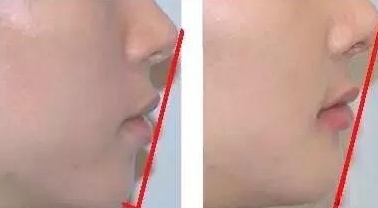

你可以用直尺子连接鼻尖-上嘴唇-颏(两腮和嘴的下面)试一下。

正常的三点应该是在一条直线上,假如这三点没有连成一条线,通常是两腮和嘴的下面没在同一条线上,就说明你的美学线不正常。

左图下颌后缩,上颌前突 右图为正常下巴

说明你存在上颌前突,下颌后缩等问题,而美学线不好看则直接影响了整个面部侧面的美观。